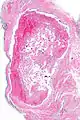

Intravascular papillary endothelial hyperplasia

Intravascular papillary endothelial hyperplasia is a rare, benign tumor. It may mimic an angiosarcoma, with lesions that are red or purplish 5-mm to 5-cm papules and deep nodules on the head, neck, or upper extremities.[1][2]: 592

Histopathology Images